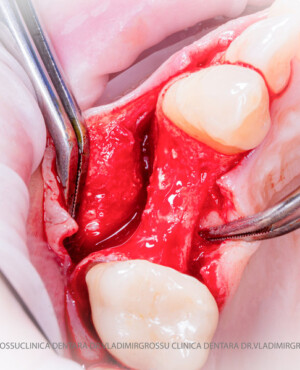

Un element esențial în procedura de aditie osoasă este utilizarea membranelor biologice, care izolează materialul osos de țesuturile moi (gingie) pe durata procesului de vindecare. Cele mai recomandate sunt membranele resorbabile din colagen sau pericard.

Aditia gingivală este o procedură chirurgicală ce corectează diverse probleme estetice și funcționale, cum ar fi recesiunea gingivală. În implantologia modernă, aditia de țesut moale este utilizată aproape în fiecare intervenție de inserție a implantului dentar pentru a asigura un aspect estetic natural și o bună integrare a implantului în cavitatea bucală.